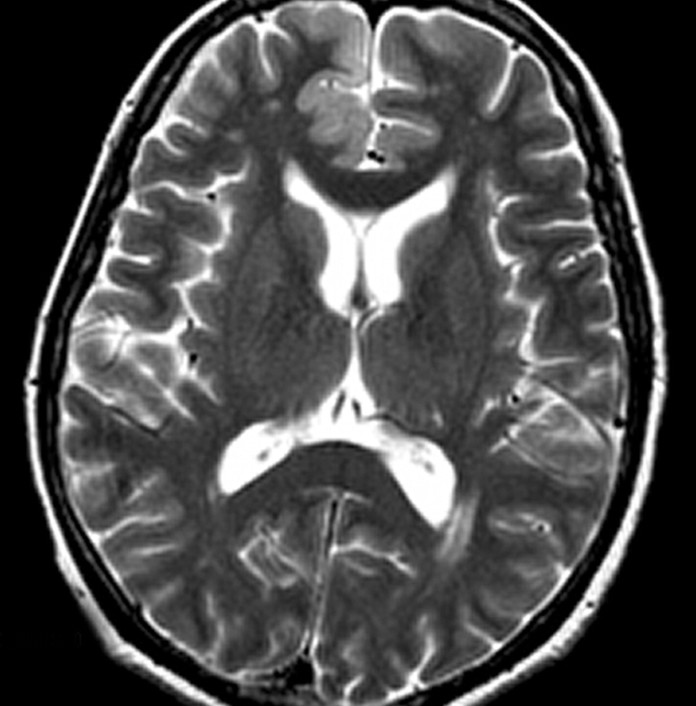

La enfermedad de Creutzfeldt-Jakob es una enfermedad rara, el cerebro se involucra en una demencia que progresa rápidamente. Los nuevos casos aparecen en cerca de una persona por millón cada año en el mundo y la confirmación del diagnóstico es un reto. Las personas con la enfermedad puede tener una amplia gama de síntomas. Muchas otras condiciones pueden causar síntomas similares, y con algunas de estas condiciones, la demencia puede ser tratada.

La guía se centró sólo en el diagnóstico de la enfermedad de Creutzfeldt-Jakob esporádica. Mientras que varias pruebas están disponibles para diagnosticar la enfermedad de Creutzfeldt-Jakob esporádica enfermedad, la biopsia cerebral es la prueba más exacta que se puede realizar en una persona que vive con la enfermedad. La biopsia cerebral es potencialmente peligrosa.